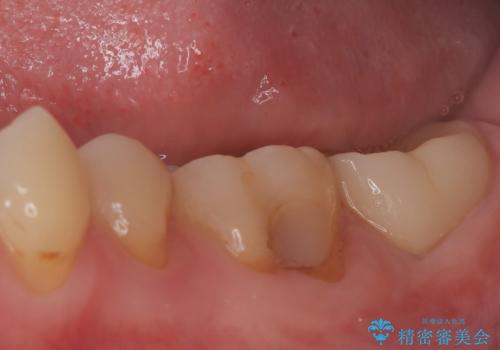

- 患者様は、他院で根管治療を受けたものの、違和感が続くため「しっかりとした治療を受けたい」とのご希望で来院されました。診査の結果、根管内の感染が完全に除去されておらず、根の先に炎症が残っている状態でした。そこで、精密根管治療を行い、感染源を徹底的に除去する計画を立てました。マイクロスコープを使用し、4回の治療で根の内部を清潔にし、最終的にしっかりと密封することで、長期的な安定を目指しました。

治療は、まず根管内の古い充填材を取り除き、感染部分を徹底的に洗浄・消毒することから始めました。ラバーダム防湿を使用し、治療中の細菌感染を防ぎながら、マイクロスコープを用いて根管の細部まで確認しながら処置を進めました。4回の治療で感染の除去と根管の封鎖を行い、最終的に土台を立てて被せ物の準備を整えました。患者様からは「違和感がなくなり、噛んでも痛くない」と喜びの声をいただきました。